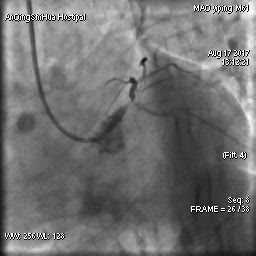

由于毛先生的病變涉及主干分叉,即復(fù)雜的真性分叉病變,為保證分支開口得到良好的開放,術(shù)者采取了操作復(fù)雜的雙支架術(shù)式,先后運(yùn)用掏支架網(wǎng)眼、球囊擴(kuò)張、雙球囊對(duì)吻擴(kuò)張、POT技術(shù)等,實(shí)現(xiàn)了完全血運(yùn)重建。術(shù)后,毛先生的嚴(yán)重心絞痛終得緩解。

術(shù)后 心臟左主干末端狹窄解除,血流通暢